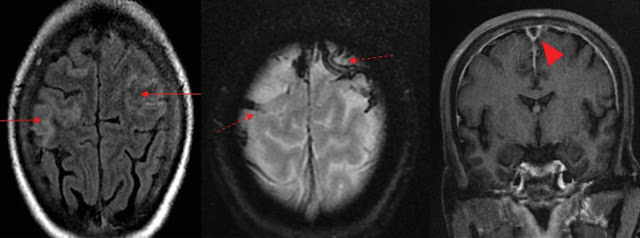

(a): Axial Fluid Attenuated Inversion Recovery (FLAIR) image

depicting mild gyral oedema in bilateral high frontoparietal lobes (red

arrows). (b): Gradient Recalled Echo (GRE) image showing blooming in cortical

veins in bilateral high frontal lobes (red dashed arrows). (c): Post contrast

T1 coronal image showing filling defect in superior sagittal sinus suggesting

thrombosis (red arrow head).